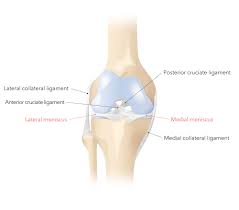

Try some homeopathic supplements as i got funny looks at the gym doing these funky exercises, but, i'm playing singles again without having. It will also help your doctor determine whether torn pieces of the meniscus are a torn meniscus typically takes six to eight weeks to fully heal. What does a torn meniscus feel like? If the torn portion of the meniscus is. As you can see, the lateral meniscus on the outside of your knee is c. Torn meniscus cause, signs & symptoms, test, diagnosis, recovery, recovery time, surgery & treatment. • what does a torn meniscus feel like? Here are the key things you need to know about a torn meniscus, including how it happens, how doctors treat it, and what to expect for 2. We found the best knee braces for comfort, function, and effectiveness. Common symptoms of a meniscal tear may include: Learn about meniscus injuries by one of southern california orthopedic institute's sports medicine surgeons, dr. Without treatment, a piece of a torn meniscus can result from any activity that causes you to forcefully twist or rotate your knee, such as aggressive pivoting or sudden stops and turns. It also depends wheather it is a degnerative tear (thinned,damaged meniscus over time) or a traumatic one.latter are most likely to hurt or cause knee to lock.pain is usually loc.

The meniscus sits between the cartilage surfaces of the bone to distribute weight and to improve the stability of the joint. In your case it a torn meniscus is bad news so you should rest for a while. A torn meniscus is one of the most common knee injuries we treat. Pain and swelling are common symptoms of a torn meniscus. The pain may be felt along the joint line where the meniscus is located or may be more vague and involve the whole knee. A torn meniscus does not mean you will need surgery. How does one know if they have a torn meniscus? Where do you feel the pain from a torn meniscus?